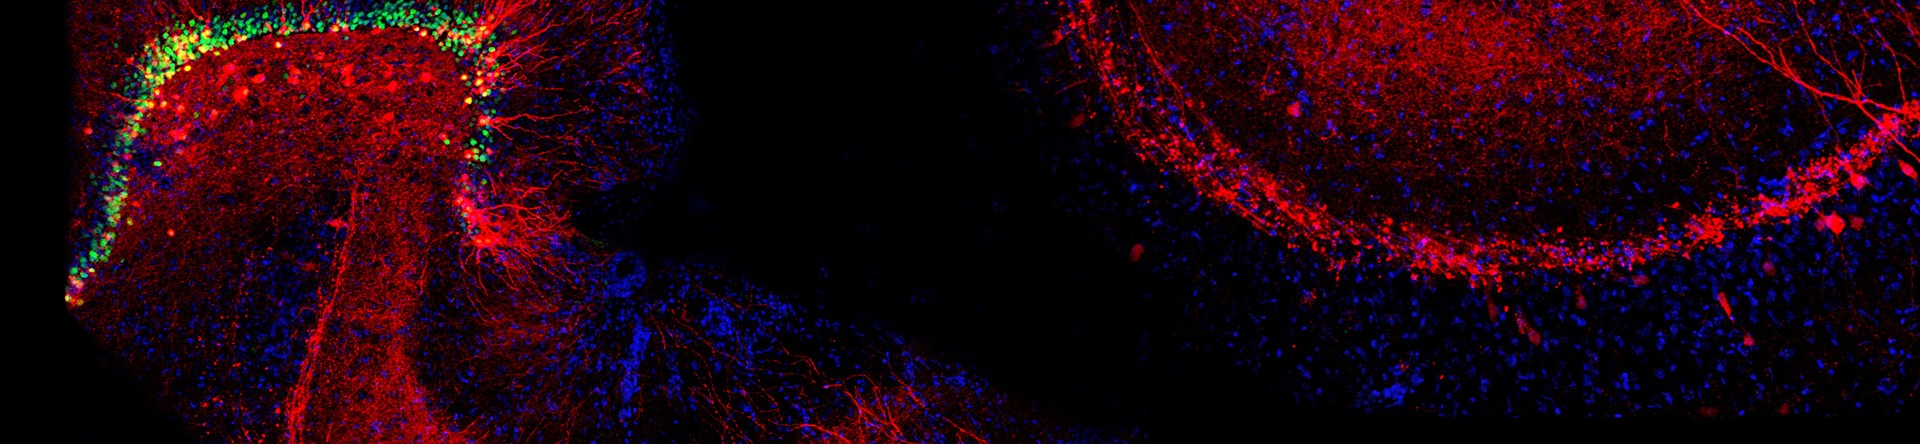

Brain Diagram

Using transgenic technologies, we pursue the study of how heritable and de novo genetic variation in transporter genes leads to risk for neurological disorders. These studies initiate from identification of transporter genetic variation in humans with a range of disorders. Over the past decades we have identified such variation in subjects with autonomic dysfunction, neuromuscular disorders, ADHD and bipolar disorder, and autism. In subsequent efforts, we have generated the first mouse model of perturbed dopamine signaling in ADHD. Ongoing studies look to contribute both human and mouse model efforts to disorders with deficits in acetylcholine and glutamate signaling. To these studies, we bring our substantial know-how in synaptic biochemistry and anatomy as well as physiological and behavioral methods. Our goal is not to reproduce all of the facets of a given disorder in the model. Such an effort naively assumes that all facets of human physiology and behavior can be reproduced in a rodent model. Rather, we seek to understand how changes at a molecular, cellular and organismal level can emerge when synaptic transporters are not working well, leading to both new fundamental insights into potential gene networks and affording the development of novel medications that can manipulate these networks to benefit those afflicted with brain disorders. We also capitalize on a rich battery of transgenic mice (and worms) that carry specific alterations in brain signaling pathways allowing us to further dissect components of these networks, and to determine which components, where in the brain, and when in development, are effects levied to to perturb physiology and behavior.